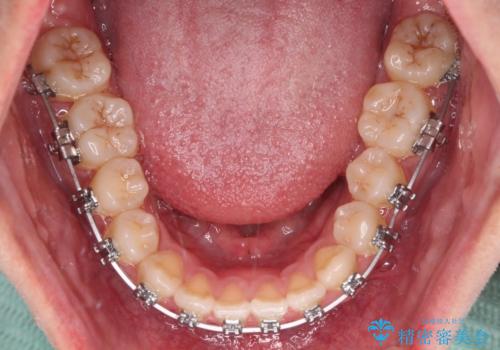

- メタルブラケット

上顎歯列が狭窄していたため、急速拡大装置により上顎骨を側方に拡大し、その後ワイヤー装置にて矯正治療を行うこととしました。

上顎骨を拡大することで、八重歯やデコボコを歯列に収めることができ、下顎の歯が外に位置していた奥歯の咬み合わせも改善することができました。

スペースも短期間に獲得できるため、1年程度で治療を終えることができました。